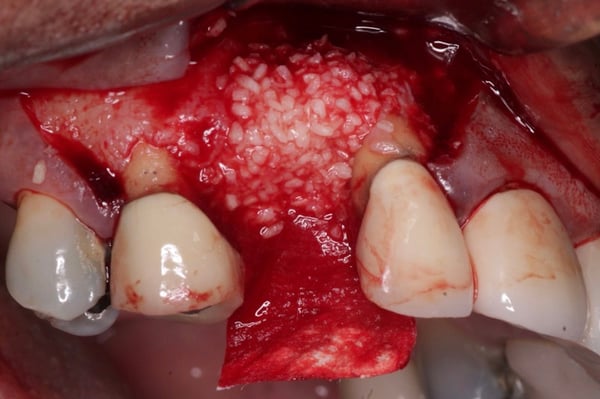

Instead of using a traditional particulate graft covered with a resorbable membrane, a “flexible bone graft” sheet, DALI Flex Graft, was placed over the buccal plate to augment the buccal contour (Pictures 6 & 7). Because the graft comes hydrated, it is easy to handle and adapt to the defect location. The flap was then pulled over the graft and adapted around the healing abutment (Picture 8).